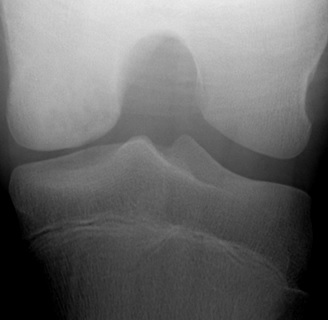

Tunnel view of osteochondritis dissecans

From the collection of H. Chambers, MD